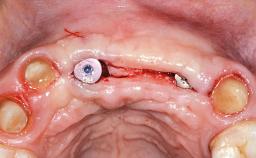

In 2001, a 48-year-old woman presented at a dental clinic with a failing fixed partial denture spanning from teeth 13 to 21. She was experiencing pain upon function, tenderness to palpation facial to tooth 13, and severe mobility of the prosthesis. Radiographic and clinical assessment revealed a subcrestal fracture of tooth 13, making its restoration unlikely. It was determined by the clinician that the tooth needed to be extracted prior to proceeding any further with dental care. After the extraction, the patient lost confidence in the progression of her treatment and sought consultation at the Center for Implant Dentistry. At her consultation visit in our clinic, an extra- and intraoral clinical examination revealed a medium lip line at full smile and an edentulous area spanning from 13 to 12 with both vertical and horizontal deficits in hard and soft tissue.

Soft Tissue Anatomy Intact Defective

Bone Volume Horizontally and vertically sufficient Horizontally deficient Deficient vertically or deficient vertically AND horizontally